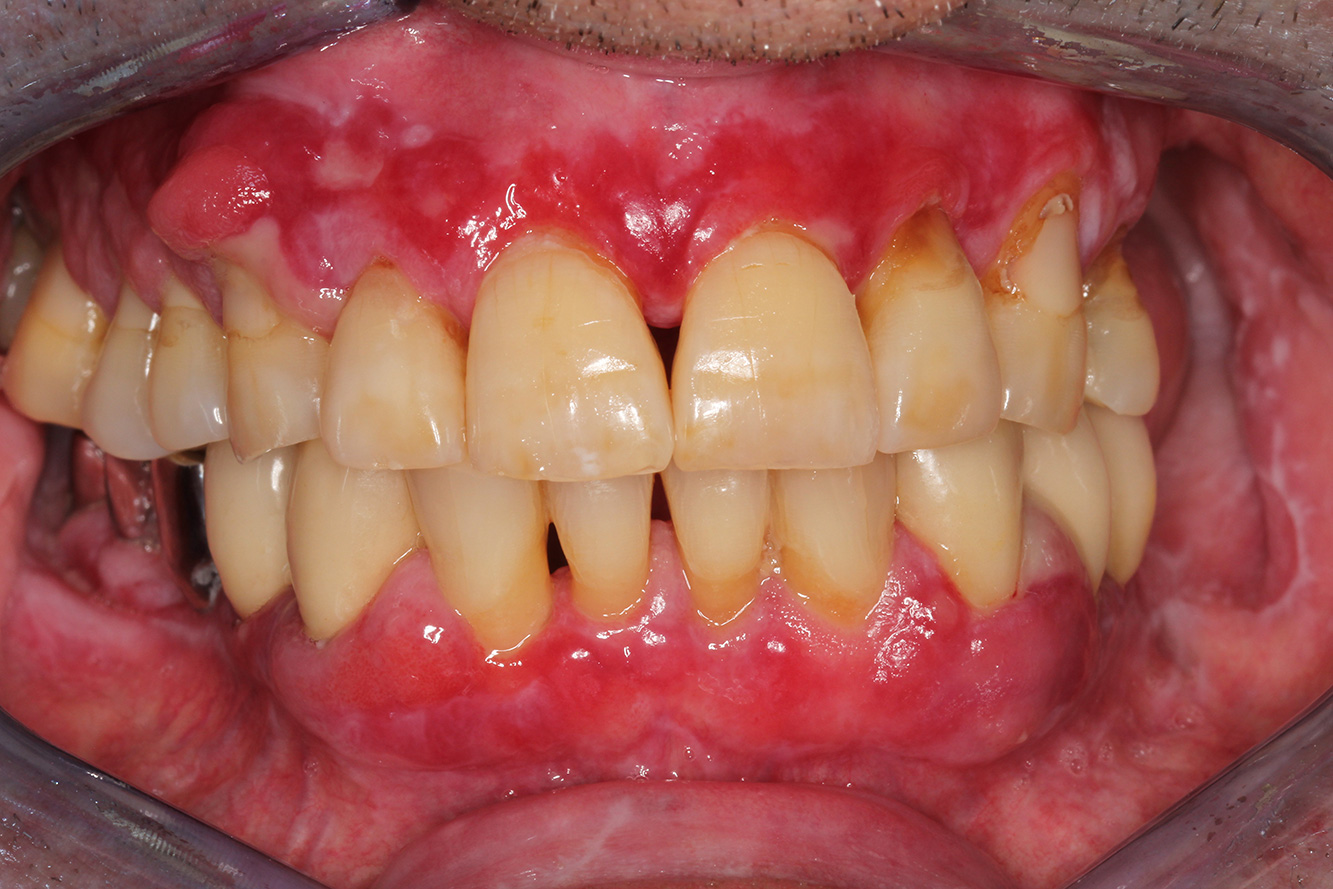

Se presenta un paciente de 71 años con trasplante de riñón e hipertensión (presión arterial alta). Debido a su historia médica, es necesario el tratamiento continuo con ciclosporina para suprimir el sistema inmunitario y amlopidina para bajar la presión arterial. Además, el paciente relata encías sensibles y sangrantes. Desde el punto de vista de la salud oral, hay dientes restaurados con ocho piezas faltantes, hiperplasia gingival pronunciada, periodontitis en fase II, de grado B con bolsas activas y una caries inicial en la pieza 22. En la evaluación del riesgo de caries se ha establecido un riesgo de caries medio (API 60). Para la sesión de profilaxis se hacen las siguientes recomendaciones.

Con base en la historia médica, se detecta un riesgo de complicaciones importante. Debido al trasplante de riñón, el paciente está inmunodeprimido (ciclosporina), también tiene el sistema inmunitario debilitado y necesita profilaxis para infecciones (recomendación: 2 g de amoxicilina como antibiótico 1 h antes de la sesión). Al mismo tiempo, el tratamiento continuo hace que el paciente tenga un mayor riesgo de enfermedad, dado que la hiperplasia gingival establecida está asociada a la medicación (20).

Se debe abordar la situación del paciente, especialmente cuando se trata de motivación y aprendizaje. La hiperplasia gingival dificulta la higiene oral en casa. La mayor susceptibilidad a las infecciones y el progreso y la nueva formación de hiperplasias (22) debe hablarse de igual a igual. Al mismo tiempo, deben explicarse las técnicas de higiene adecuadas según las necesidades individuales.